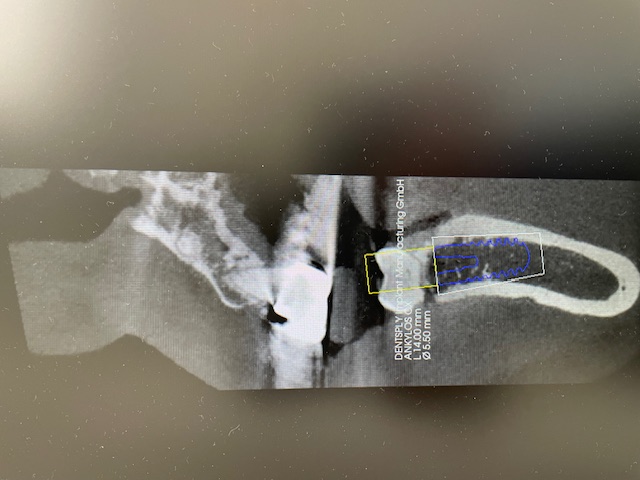

歯科用CT

CT

歯や顎の状態を3次元の立体画像で確認できます。